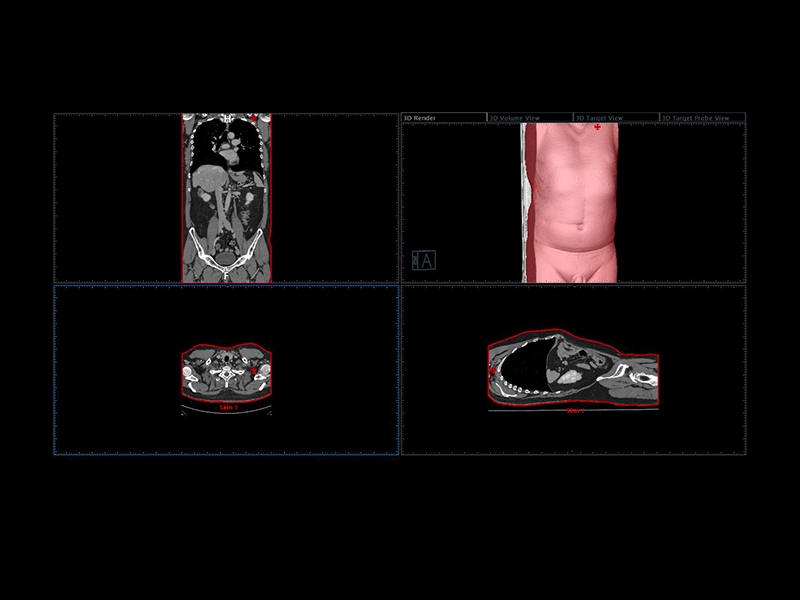

MyLab™X90 - UroFusion Automatic segmentation of the prostate MRI/US, followed by autoregistration of both modalities for targeted biopsies

MyLab™X90 - UroFusion Automatic segmentation of the prostate MRI/US, followed by autoregistration of both modalities for targeted biopsies